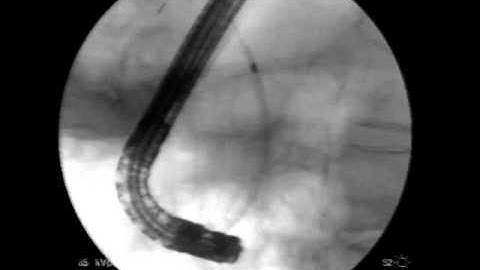

Ercp, nội soi mật tụy ngược dòng dùng needle - knife và stent Metallic